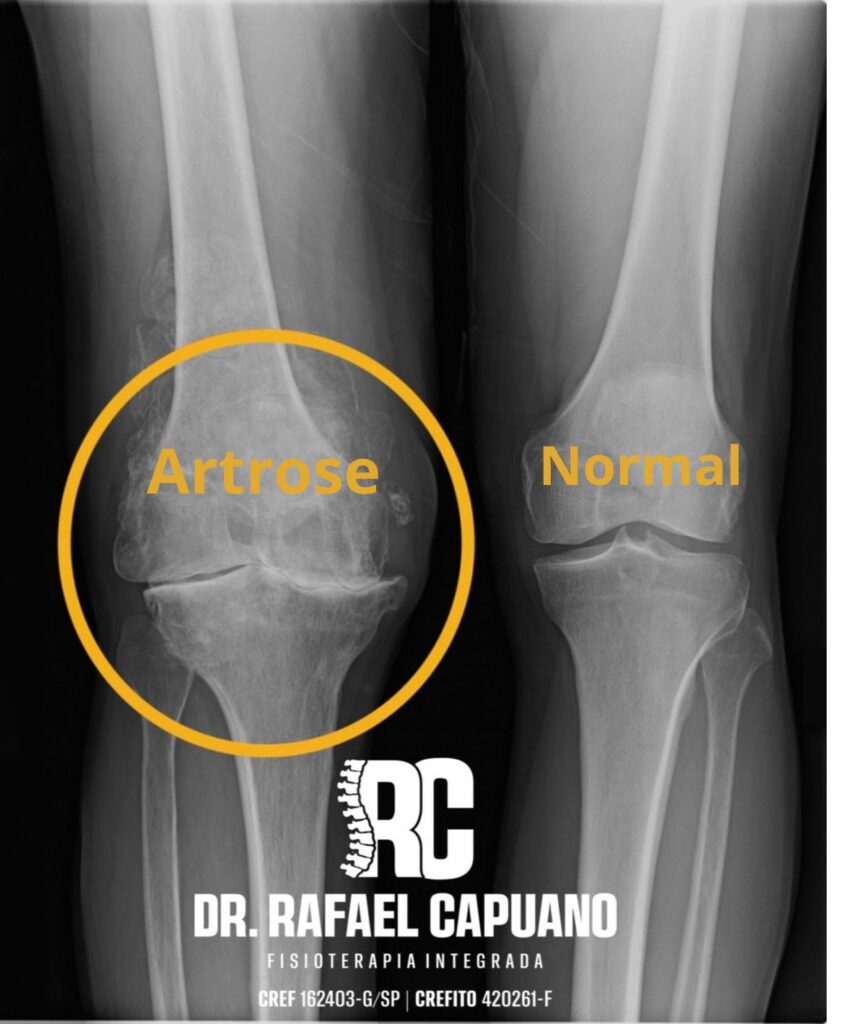

A artrose, também chamada de osteoartrite, é uma das condições articulares mais comuns no mundo. Ela causa desgaste progressivo da cartilagem, tecido responsável por amortecer o impacto e permitir o movimento suave entre os ossos. Quando essa cartilagem se desgasta, o atrito aumenta, surgem inflamações, dor e limitação nos movimentos.

As articulações mais afetadas são: Joelhos e quadris, por suportarem o peso corporal; Coluna, devido à sobrecarga postural; Mãos e dedos, pelo uso constante em tarefas repetitivas.